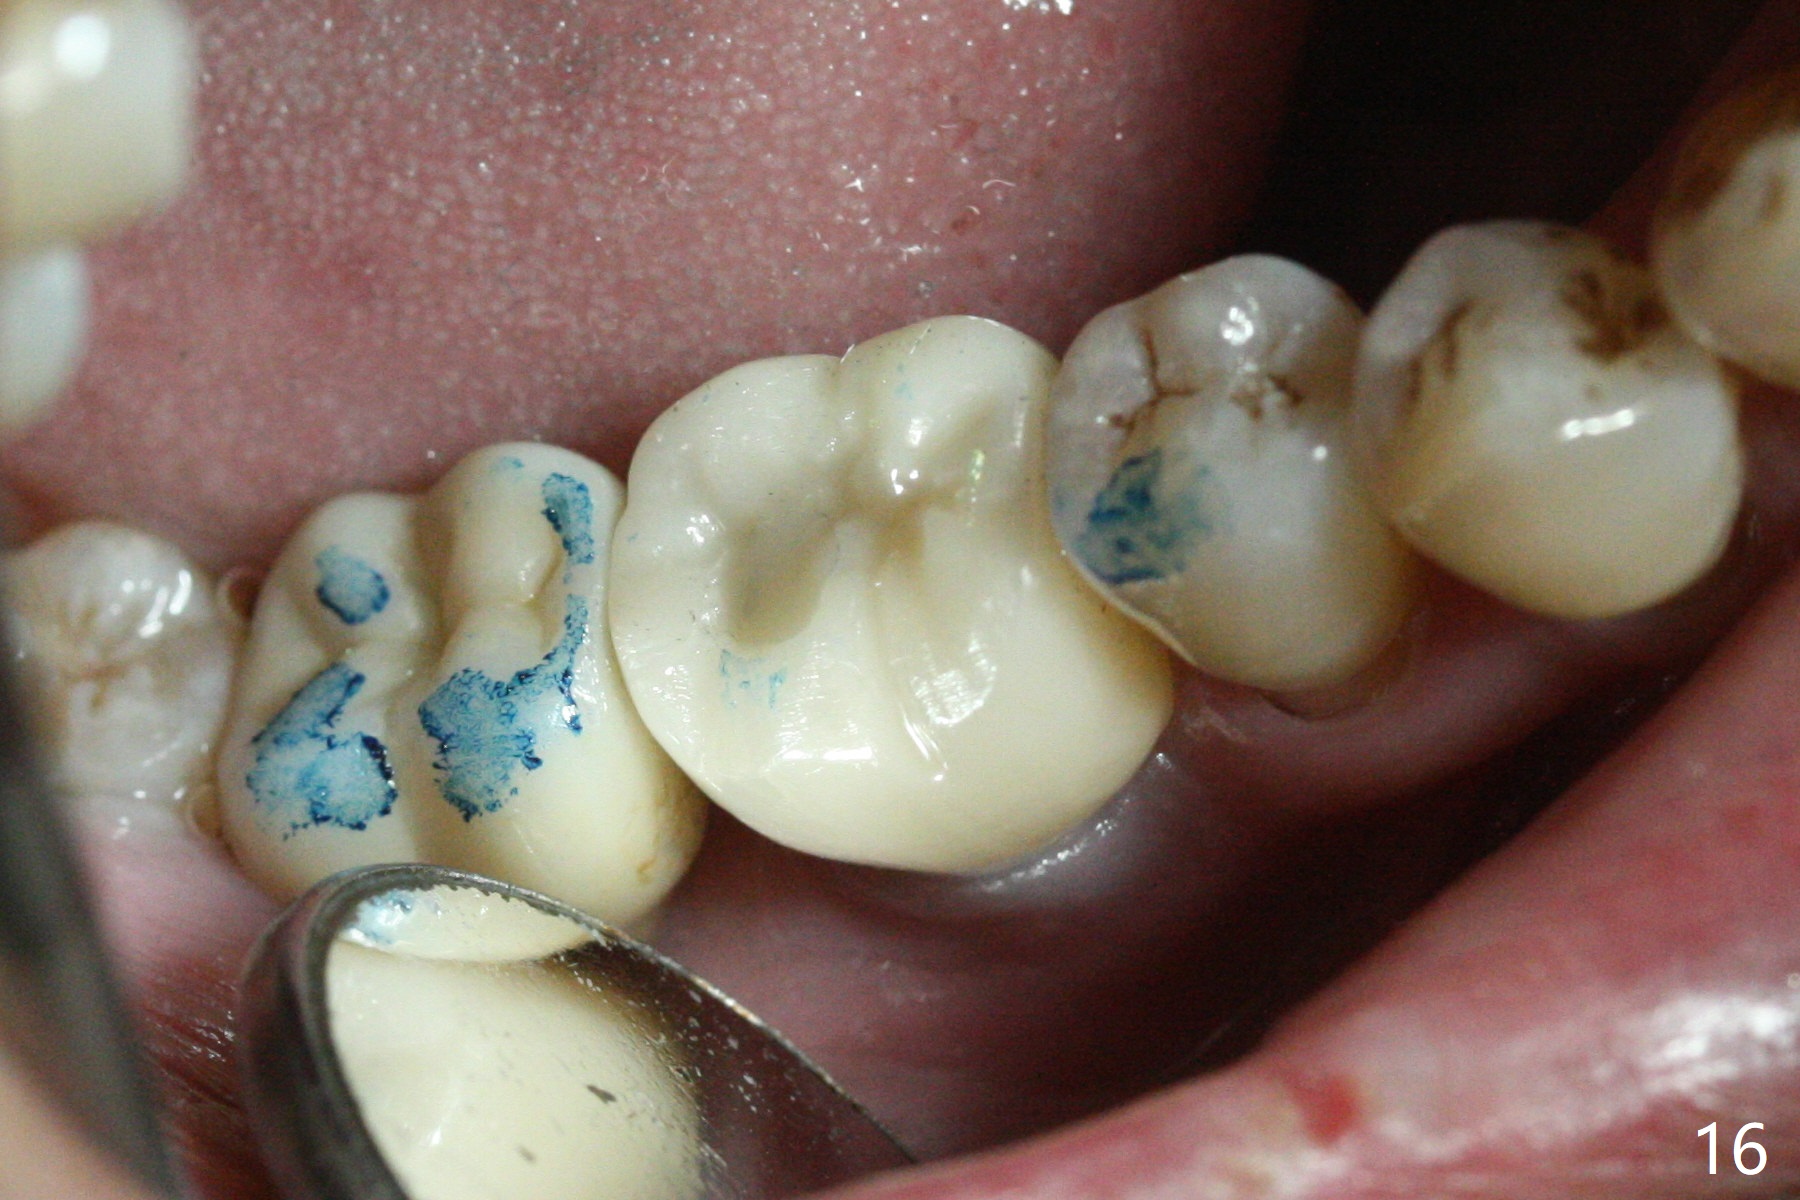

Extraction shows the large distal socket (Fig.1 D) and the thin and low septum (*) of the tooth #30. After Magic Split test confirms hard bone, osteotomy is initiated with 1.6 mm pilot drill with 11 mm stopper (Fig.2); there is 2.7 mm distance to the Inferior Alveolar Canal. Following Marking Bur, a 4.8 mm Magic Drill is used to finish the osteotomy with difficulty because of hard bone and ineffective local anesthesia due to infection. A 5x9 mm "dummy" implant is placed to determine the placement level relative to the distal crest (Fig.3 *). After removal of the dummy implant, an authentic one with the same dimension is placed with packing abundant allograft (.5-1.5 mm) and Osteogen (Fig.4 *); it appears that 4 to 5 threads (fins) of the implant (arrowheads) are engaged to the native bone for primary stability (>40 Ncm). Later more bone graft is placed distally (Fig.5 arrow). With the short implant placed not so deep, there is 6-7 mm clearance from the underlying canal (Fig.6). The patient is doing well 7 days postop (Fig.7). He feels that the provisional is too bulky buccally for the first 2 days postop. The buccal margin will be trimmed in another 2 weeks (dashed line). The patient in fact masticates on the right side postop. By the time he returns for provisional revision 1 months 10 days postop, he has mild pain. There is food entrapment. The provisional and the abutment are slightly loose, whereas the implant is stable with healing socket (Fig.8). A healing abutment is placed. The implant appears unstable nearly 5.5 months postop. The gap between the bone and implant seems to be large (Fig.9). The implant should have been larger and longer for fast healing. A healing screw is used instead. The site heals 10 months postop with an increase in bone density around the implant (Fig.10.) Prior to cementation of the final crown, the abutment is minimally exposed (Fig.11 (6.5x5.7(3) mm)). In fact the abutment screw becomes loose 2 months post cementation (1 year postop); it appears that crown/implant ratio is unfavorable (Fig.12). The implant is slightly placed mesially (cantilever). The patient cannot chew on the left. The tooth #19 is periodontally affected and the tooth #18 is missing. When bone loss is severe, the implant should be as large as possible and preferably tissue-level. The abutment screw is re-loosening 1.5 years post cementation (4 months post #19 socket preservation, Fig.13). The crown/implant ratio at #31 is more favorable than that at #30 (compare black lines). The crown at #31 has large contact area with the tissue-level implant (external), whereas the contact between the abutment and the bone-level implant is much less (internal). To prevent the abutment screw re-loosening (turning) in function, a screw driver (Fig.14 D) will be buried inside the crown/abutment after the screw is retightened. Make sure that the driver is in the middle of the access hole. Section the driver in situ obliquely (Fig.15); flat sectioning allows the driver to turn with the abutment screw in function. After insertion of plumber tape around the sectioned screw driver, use composite to fix the driver in place and seal the access hole (Fig.16). Occlusal check suggests weak link between the abutment and bone-level implant at #30.